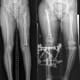

Join us for the 4th Annual UCSF/IGOT Pediatric Limb Differences educational event, an engaging, case-based webinar exploring the latest global strategies for managing post-traumatic lower limb deformities in children. Led by a panel of national and international experts, this interactive session will provide valuable insights and real-world solutions to enhance patient care.

Discuss the comprehensive management of a child with post-traumatic lower limb differences in diverse practice settings

Explore unique strategies for managing sequelae of injuries to the growth plate

Review different options for addressing post-traumatic malunions

Using case-based discussions, identify management strategies for post-traumatic bone loss, including amputations and blast injuries